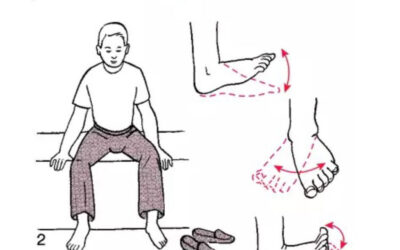

Foot Rehabilitation Exercises for Flatfoot: A Case Study

Pes planus is also known as flatfoot. It comes from Latin word that means pes as foot and planus as flat or ground level. Here, the medial longitudinal arch of the foot descends, resulting in a lack of spring action and increased stress on the entire foot with each step. It serves as an adaptive support base for the entire body, functions to…

By Pradhyum D. Kolhe , H V Sharath , Siddhi G. Rathi , Deepali S. Patil